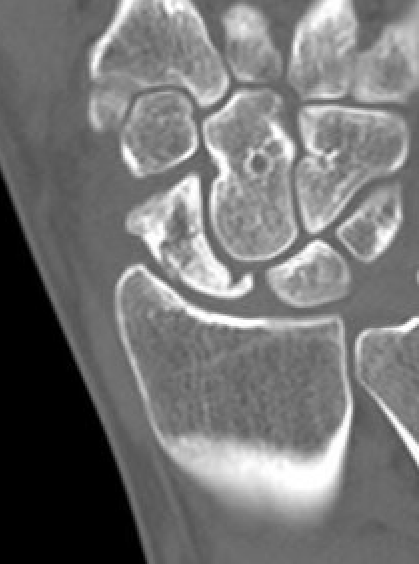

CT

Increased sclerosis of the proximal pole

Fragmentation and collapse of the proximal pole